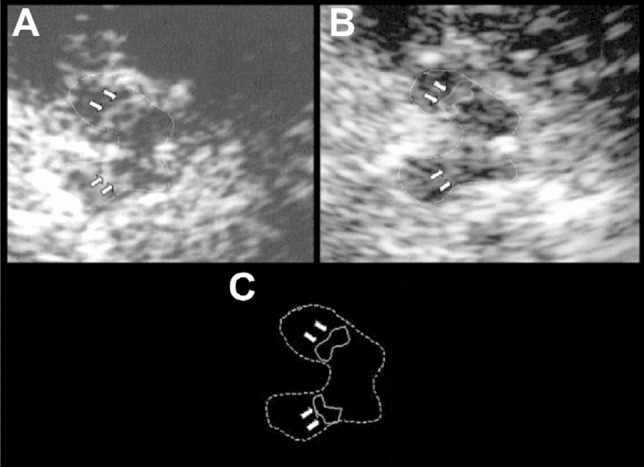

Fig. 6

Transcranial ultrasonogram showing progressive hyperechogenicity of the substantia nigra pars compacta in Parkinson disease. a Initial examination revealed an area of 0.23 cm2 hyperechogenicity in the substantia nigra pars compacta (white arrows). b Follow-up examination at five years showed hyperechogenicity had not changed. c Schematic representation of the ipsilateral mesencephalon, with the substantia nigra pars compacta marked with white arrows. Reproduced from (Berg et al. 2005) with permission from

John Wiley and Sons (copyright 2005)

Transcranial ultrasonography was also applied to assessing brain iron in the mid-1990s. Hyperechogenicity of the substantia nigra, viewed through the temporal bone window, is increased in Parkinson disease. First reported in 1995 by Georg Becker and colleagues (Würzburg), it was initially attributed to nigral gliosis and regarded as being correlated with disease severity and duration (Becker et al. 1995). Daniela Berg, who had detected nigral iron accumulation and increased echogenicity in 6-OHDA-treated rats (Berg et al. 1999b), confirmed that hyperechogenicity was a cost-effective means for screening for the iron accumulation in the basal ganglia (Berg et al. 1999a2002; Berg 2009). She and her colleagues also found that nigral hyperechogenicity developed early—indeed, before the emergence of any symptoms (Berg et al. 2011)—and did not change in the course of the disease (Berg et al. 2005; Fig. 6), leading to transcranial ultrasonography being included in the Movement Disorders Society research criteria for identifying people at increased risk of Parkinson disease (Berg et al. 2015).